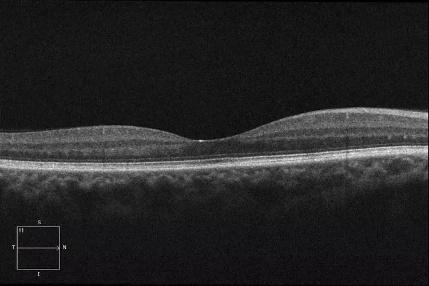

在日常生活中,我们常常听到“中奖”这样的词汇,它代表着幸运和喜悦。然而,今天我们要聊的却是一个与“中奖”谐音,却截然不同的健康话题——“中浆”,全称为中心性浆液性脉络膜视网膜病变。“中浆”是一种由于脉络膜血管通透性增强,继发视网膜色素上皮屏障功能受损所导致的局限性视网膜神经上皮脱离的眼底疾病。

“中浆”的OCT影像